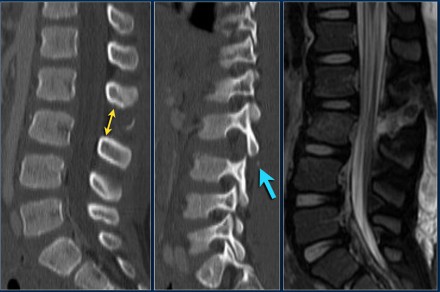

The findings are:

- Morphology: Burst - 2 points

There is retropulsion of a body fragment (black arrow) - PLC: widening of both facet joints (yellow arrow) and a fracture of spinous process (blue arrow) - 3 points

- TLICS based on imaging: 5 points

Discussion: based on only

these two images it is hard to say whether this is burst with

PLC-injury or maybe distraction on the posterior side.

In either case the TLICS-score is high and this patient is a surgical candidate.